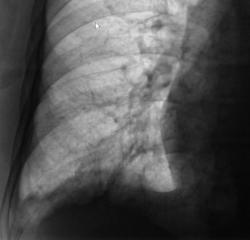

Сегодня произвели "очередной контроль". Произвели рентгенографию в прямой и правой боковой проекциях. Решили также произвести томографию в правой боковой проекции.

Катенёву В.Л.: На боковых томограммах, впечатление о инфильтрации с распадом в S10; томограммы, вероятно выполнены в положении лёжа, следовательо следует ожидать, что выпот растекся по грудной стенке и  не виден. С учётом характера распада, не исключаеиться туберкулёзный процесс.

О "выпоте" думали даже сначала, но только об осумкованном. Сегодня при дообследовании, "полостное образование" было неожиданной находкой, но о "туберкулёзной" этиологии, именно полостного образования, не думали. Но интересно, что пациент себя (с его слов) чувствует себя хорошо. ПО ВСЕЙ ВИДИМОСТИ, ОТПРАВИМ В ОБЛАСТЬ К ПУЛЬМОНОЛОГАМ.